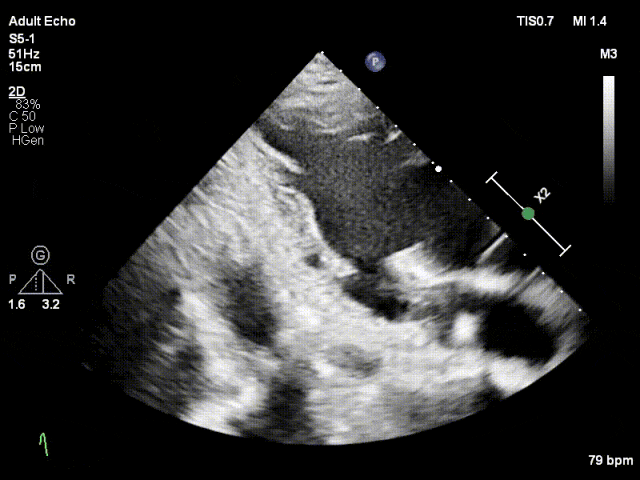

对应策略

术前张小勇教授、段鹏教授团队与陈样新教授、邓冰清教授经充分沟通及分析,决定术中在2区植入一枚长宽(XW0612)型号DragonFly™二尖瓣夹,夹闭后评估残余脱垂及反流决定是否置入第二枚夹子。术中房间隔穿刺高度3.5cm,于2区植入一枚长宽(XW0612)夹,术中患者经食道超声影像质量差,进入瓣下后无法看清前后叶,采用经食道超声结合经胸超声进行瓣叶捕获,术后反流降至轻度,跨瓣压差1mmHg,肺静脉逆流消失。

缓慢关闭夹合角度至30°

关闭瓣膜夹

L侧残余微量功能性反流

TMPG:1mmHg

肺静脉逆流消失